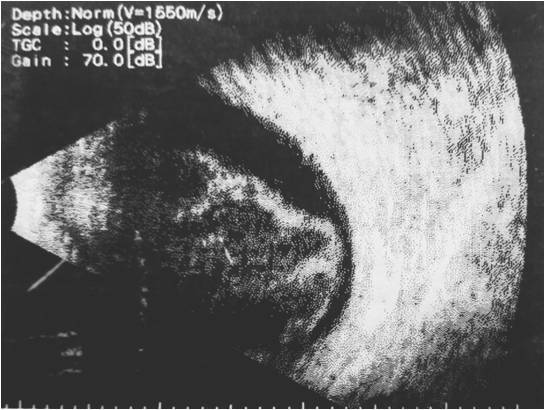

УЗИ глаза: кровоизлияние в стекловидное тело